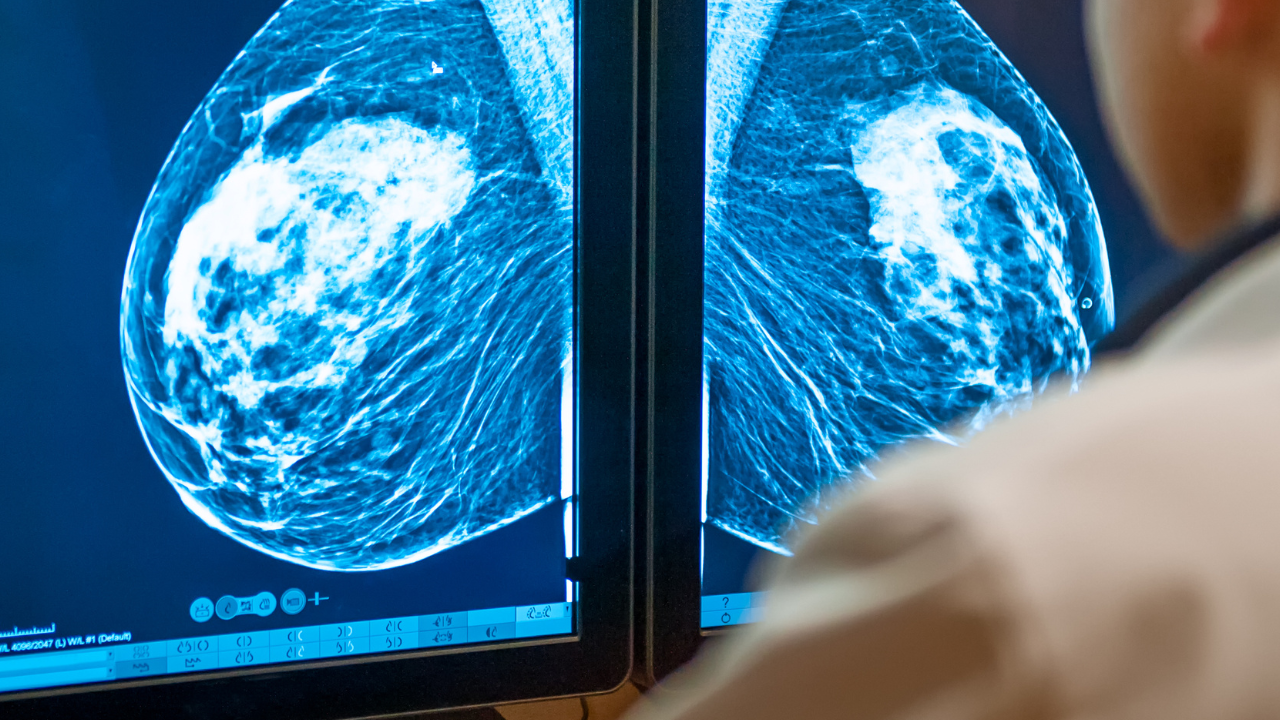

3Dマンモグラフィ(トモシンセシス)とは?

乳がん検診で知っておくべき「高濃度乳腺(デンスブレスト)」

マンモグラフィと乳房超音波(エコー)検査の違いとは?乳がん検診の選び方